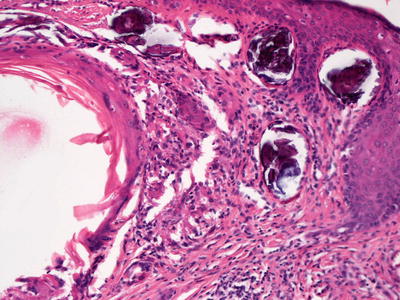

Lichen amyloidosis has a similar histologic appearance to macular amyloidosis, but the epidermis demonstrates lichen simplex chronicus-like changes (Fig. 16.30). Hyperkeratosis sits atop an acanthotic epidermis with hypergranulosis and elongation of the rete ridges. Eosinophilic deposits are present within the elongated papillary dermal tips (Fig. 16.31). Rare dying keratinocytes may be seen. Melanophages are present in the papillary dermis along with a scant lymphocytic infiltrate. A familial lichen amyloidosis syndrome is also described [196, 197].

A324456_1_En_16_Fig30_HTML.jpg

Fig. 16.30

The stratum corneum demonstrates compact orthokeratotic hyperkeratosis and the epidermis is mildly acanthotic in lichen amyloidosis

A324456_1_En_16_Fig31_HTML.jpg

Fig. 16.31

Papillary dermal tips are expanded and filled with eosinophilic bodies (degenerating keratinocytes) in lichen amyloidosis